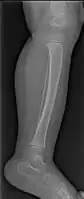

| A toddler's fracture | |

Toddler's fracture is a type of broken bone that involves the lower part of the shin bone (tibia).[1] Symptoms may include pain in the lower leg or a limp.[1] Some refuse to walk at all.[2]

The cause is often a twisting motion over a planted foot.[1] This may occur as the result tripping or other minor events.[1] It generally occurs in the distal thirds of the tibia, is undisplaced, and has a spiral pattern.[1] Diagnosis is often based on symptoms and examination, with initial X-rays appearing normal in about half of cases.[1]

The initial radiographical images may be inconspicuous (a faint oblique line) and often even completely normal.[6] After 1–2 weeks however, callus formation develops.

Accidental or innocent toddler fracture/frontal